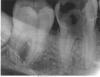

aidar Опубликовано 11 ноября, 2009 Автор Поделиться Опубликовано 11 ноября, 2009 вот, качество не очень, но другого нету Ссылка на комментарий

x3m Опубликовано 11 ноября, 2009 Поделиться Опубликовано 11 ноября, 2009 (изменено) в 6-м, похоже, 4 канала. Шансы пролечить есть.меняйте врача.открытым зуб не должен оставаться. Выполаскивать ромашкой - никакого эффекта.Врач должен пользоваться коффердамом.и надо смотреть зуб - не нравится мне бифуркация (место соединения корней). Или это просто тень? коллеги, подскажите. Если бифуркация разрушена - зуб, как правило, удаляется. ЗЫ. 8 зуб, похоже, надо удалять. сделайте еще и его снимок. Изменено 11 ноября, 2009 пользователем x3m Ссылка на комментарий

Ion Опубликовано 11 ноября, 2009 Поделиться Опубликовано 11 ноября, 2009 Моие колеги Вам правильный совет дают, чтобы Вы поменяли , и притом в срочном порядке, врача. А во-вторых, как мне кажется , 6 и 7 надо лечить, оба. И наверно в 6-ке, есть ещё перфорация. Я советю , как можно по-быстрее меняете врача. Ссылка на комментарий